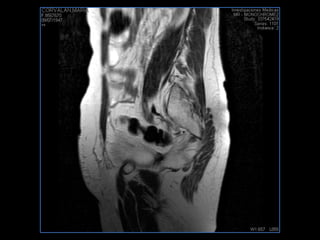

PROTOCOLO pelvis SAG T2, Y FAT SAT (FINOS) AXIAL T1  AX FAT SAT CON   GADOLINIO :  AX T1 Y COR T1 SAT: NO  FASE: RL THK: 3MM  COIL:  GAP: (FACTOR 1.4) 1MM FOV: 40 CM NEX:2 SINCRONIZACION RESPIRATORIA EN 3 O 4 CICLOS ALE